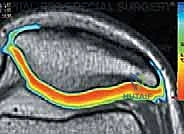

2. Magnetic Resonance Imaging (MRI): Our gold standard for cartilage assessment. MRI clearly demonstrates lesion size, location, depth, involvement of subchondral bone, and the number of lesions. Advanced sequences like T2-weighted mapping provide remarkable detail at the proteoglycan level, helping us assess cartilage quality and integrity. Postoperatively, MRI is invaluable for assessing defect fill, integration, and subchondral bone status.

FIG 3 • D,E. T2-weighted MRI mapping of articular cartilage, showing normal articular cartilage and degenerated articular cartilage.